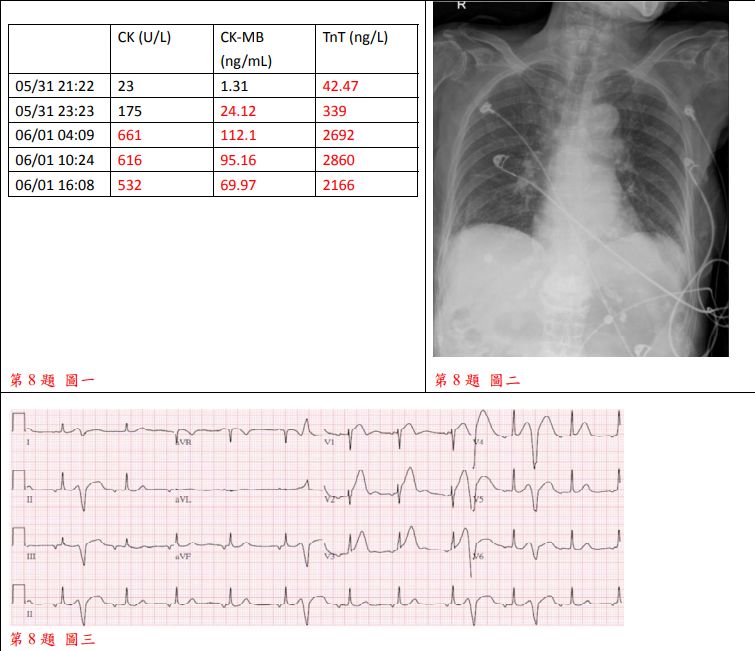

8. 86歲老太太因有二小時的胸悶前往醫院急診求治。病人在十年前因急性心肌梗塞而住院,在左前降支冠狀 動脈(Left anterior descending artery)置放冠狀動脈支架。病人尚有類風濕關節炎及老齡失智診斷。理學 檢查發現:BH:156 cm, BW:48 kg;BMI:19.7 kg/m²;T/P/R:36.2/66/22;BP:158/90 mmHg;在急診的其他檢驗尚無重大異常,其系列的生化檢驗、Chest X ray、心電圖如附圖:

(A) 高血壓性心臟病 (B) 左迴旋冠脈栓塞之Non-STE acute myocardial infarction (C) 左前降支冠脈栓塞之Non-STE acute myocardial infarction (D) 左前降支冠脈栓塞之STE acute myocardial infarction (E) 左迴旋冠脈栓塞之STE acute myocardial